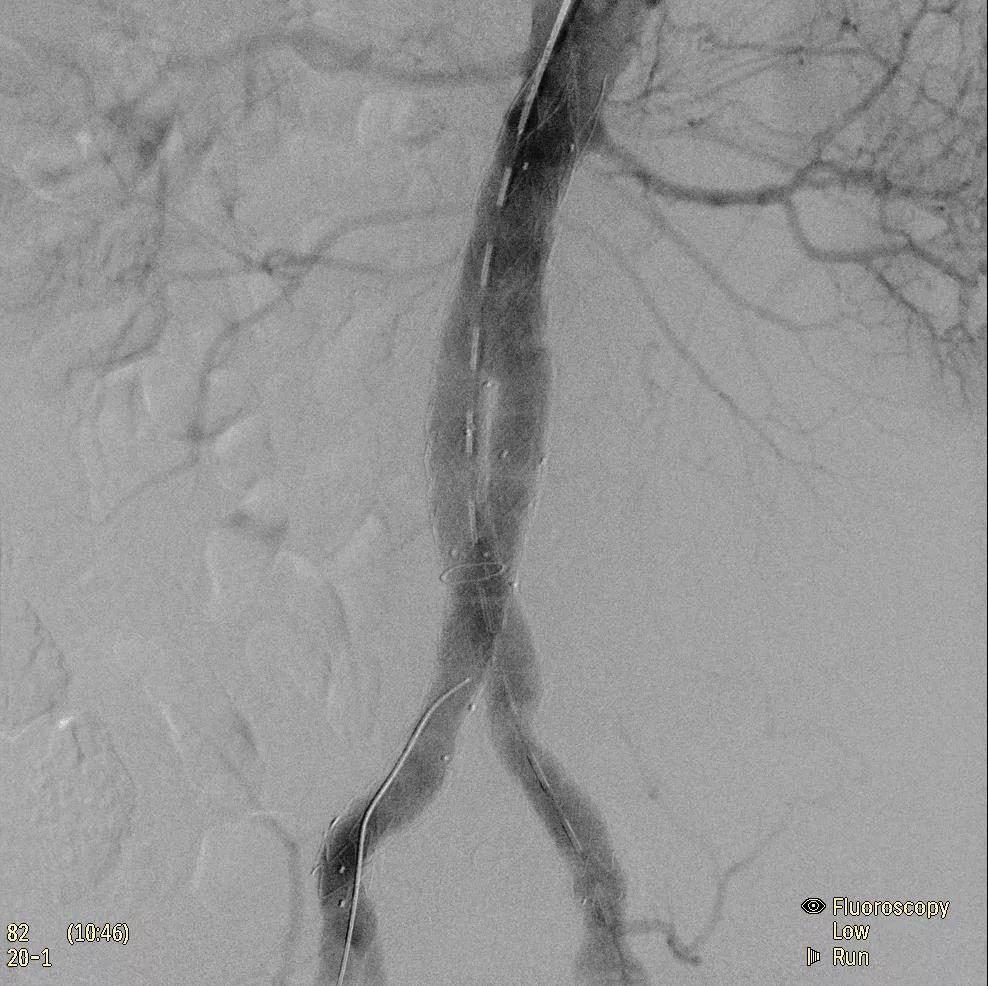

( Zenition 70采用與Azurion平臺相同的圖像處理算法。

為了獲得清晰的高質(zhì)量圖像,Zenition 70 采用了與公司Azurion平臺相同的圖像處理算法,可提供患者解剖結(jié)構(gòu)的高清可視化和更大的可視區(qū)域。飛利浦的MetalSmart軟件等功能可確保圖像質(zhì)量,該軟件可自動調(diào)整圖像的對比度和亮度,以便在視野中存在金屬物體(如植入物)時提高圖像質(zhì)量 - 這一特性使Zenition 70在整形外科中特別有用。